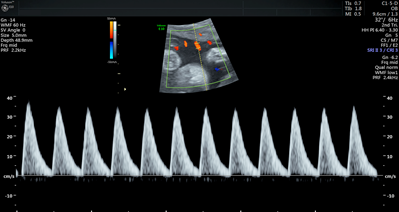

Currently, standard-of-care ultrasound scans measure blood flow at one point in the umbilical cord. The technique developed by Sled and his collaborators takes two measurements – one at the fetal end of the umbilical cord and one at the placental end. Sled says recording both measurements gives a much more accurate picture of the way blood is travelling through the umbilical cord.

“By looking at both measurements and the physics of how blood travels, we can get insight into how some of the finest blood vessels in the placenta are organized. The information this can provide to physicians is invaluable,” says Sled, who is also the Director of the Mouse Imaging Centre and a Professor and Vice-Chair in the Department of Medical Biophysics at the University of Toronto.